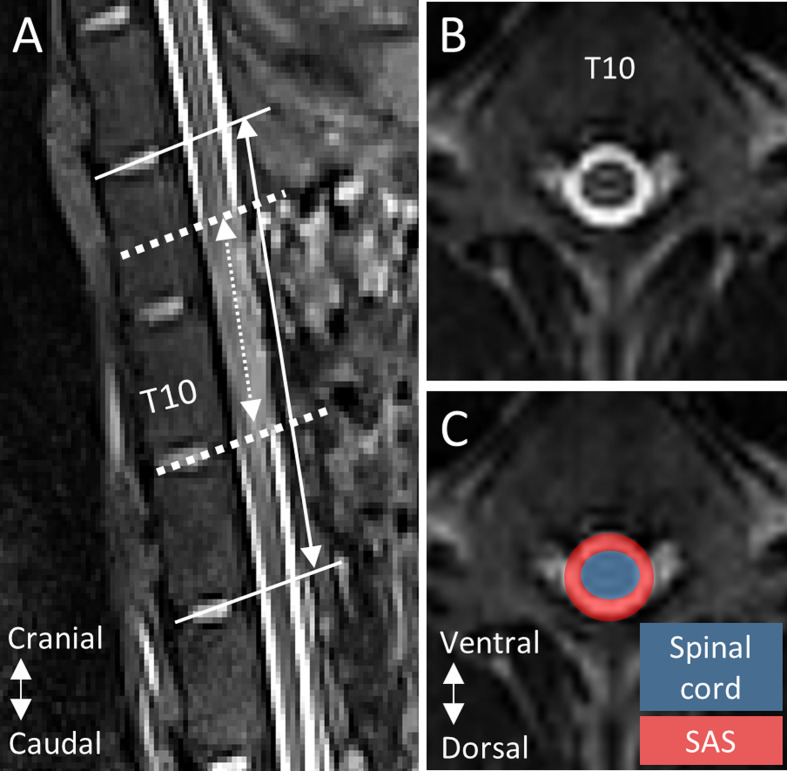

Methods: A thoracic contusion SCI was induced in female domestic pigs (22-29 kg) via a weight drop apparatus (N = 5, 10 cm; N = 5, 20 cm). Magnetic resonance imaging (MRI) was performed pre-SCI and 3, 7 and 14 days post-SCI. SAS occlusion length (cranial-caudal), and injury site SAS area (cross-sectional), were measured on T2-weighted MRI. CSF dynamics, specifically peak cranial/caudal mean velocity (cm/s), and the corresponding time to peak (% of cardiac cycle), were measured on cardiac gated, axial phase-contrast MRI obtained at C2/C3, T8/T9, T11/T12 and L1/L2. Linear-mixed effects models, with a significance level of α = 0.05, were developed to assess the effect of: (1) injury group and time point on SAS occlusion measures; and (2), time point and spinal level, adjusted by injury group, on CSF dynamics.

Results: For both injury groups, SAS occlusion length decreased from 3 to 7 days post-SCI, and 7 to 14 days post-SCI. The cross-sectional SAS area decreased after SCI, and increased to 14 days post-SCI, in both groups. At all spinal levels, peak cranial/caudal mean velocity and the time to peak caudal mean velocity decreased at day 3 post-SCI. From 3 to 14 days post-SCI, peak caudal mean velocity and the time to peak caudal mean velocity increased towards baseline values, at all spinal levels.